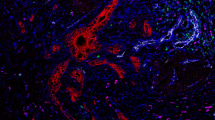

Mechanisms of Immune Resistance in Pancreatic Cancer Pancreatic cancer (PDAC) has several protections against the generation and execution of an anti-tumor hostimmune response. A) PDAC’s low antigen burden, sequestration of MHC/HLA-I molecules, and local tolerogenic TME signaling all contribute to poor immune surveillance and stunt normal dendritic cell maturation. Without normal antigen processing and presentation, anti-tumor effectors are not activated. B) If activation and clonal expansion of effector T cells still does manage to occur, trafficking to the tumor bed is complicated by disrupted chemokines gradients, abnormal vasculature, and the desmoplastic tumor stroma that acts as both a physical & chemical barrier to entry. C) Anti-tumor immune cells that are able to penetrate the TME are quickly exhausted by local metabolic conditions combined with immunosuppressive molecular crosstalk (e.g. upregulated interleukin 1 beta [IL-1b ], transforming growth factor beta [TGFb], interleukin 10 [IL-10], and beta-catenin [b-catenin]) between tumor and tumor-coopted immune cell populations (cancer-associated fibroblasts [CAF]; tumor associated macrophages [TAM]; tumor associated neutrophils [TAN]; tolerogenic dendritic cells [DC]; myeloid derived suppressor cells [MDSC]; type II T helper cells [Th2]; T regulatory cells [Treg]; B regulatory cells [Breg]). Adapted from “Challenges for CAR T-Cell Immunotherapy in Solid Tumors” and “Tumor Extracellular Matrix Reduces Therapeutic Efficiency in Solid Tumors”, by BioRender.com (2021). Retrieved from https://app.biorender.com/biorender-templates